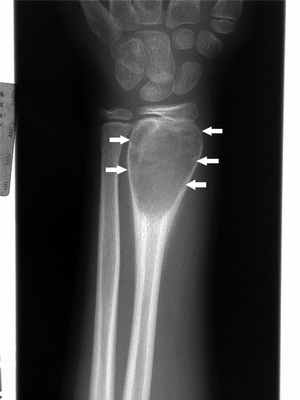

Специфические признаки злокачественности не определялись ни в одном случае (использовалась исключительно ультрасонография и КТ; рис. 1). Гистологические признаки не коррелировали ни с возрастом пациентов, ни с размерами новообразования. Все новообразования имели III категорию по классификации Bosniak. В 1 наблюдении зафиксировано нагноение мультилокулярной кисты. Нефрэктомия выполнена лишь у 1 из 6 больных. В остальных случаях использовалась органосохраняющая операция. Ни в одном наблюдении не отмечено регионарного или отдаленного метастазирования. Все новообразования были монофокальными. Пункция кисты с цитологическим исследованием аспирата проведена у 3 пациентов, и во всех случаях атипичные клетки не выявлены (в 1 из 3 наблюдений имел место ложноотрицательный результат).

Характерна рентгенологическая картина: область просветления обычно четко очерчена и расположена эксцентрично; надкостница выпячивается ("мыльные пузыри"), выдаваясь в окружающие мягкие ткани, а может быть окружена новообразованной костной тканью. МРТ обычно показывает уровень жидкости. При визуализации некоторые аневризматические костные кистовидные поражения могут выглядеть более угрожающе, напоминая по характеристикам остеосаркому, поэтому могут возникнуть подозрения на телеангиэктатическую остеосаркому Остеосаркома (остеогенная саркома) Первичные опухоли костей встречаются значительно реже, чем метастатические опухоли костей, особенно у взрослых. К первичным опухолям костей относятся множественная миелома, остеосаркома, адамантинома. Прочитайте дополнительные сведения , расположенной на самом конце кости.

Доброкачественные гигантоклеточные опухоли кости при визуализации проявляются как экспансивное литическое поражение. При визуальных исследованиях обнаруживается склеротический ободок –граница между опухолью и нормальным губчатым веществом кости. Необходимо выполнение биопсии. Поскольку гигантоклеточная опухоль кости может метастазировать в легкие, на начальной стадии проводится КТ грудной клетки.